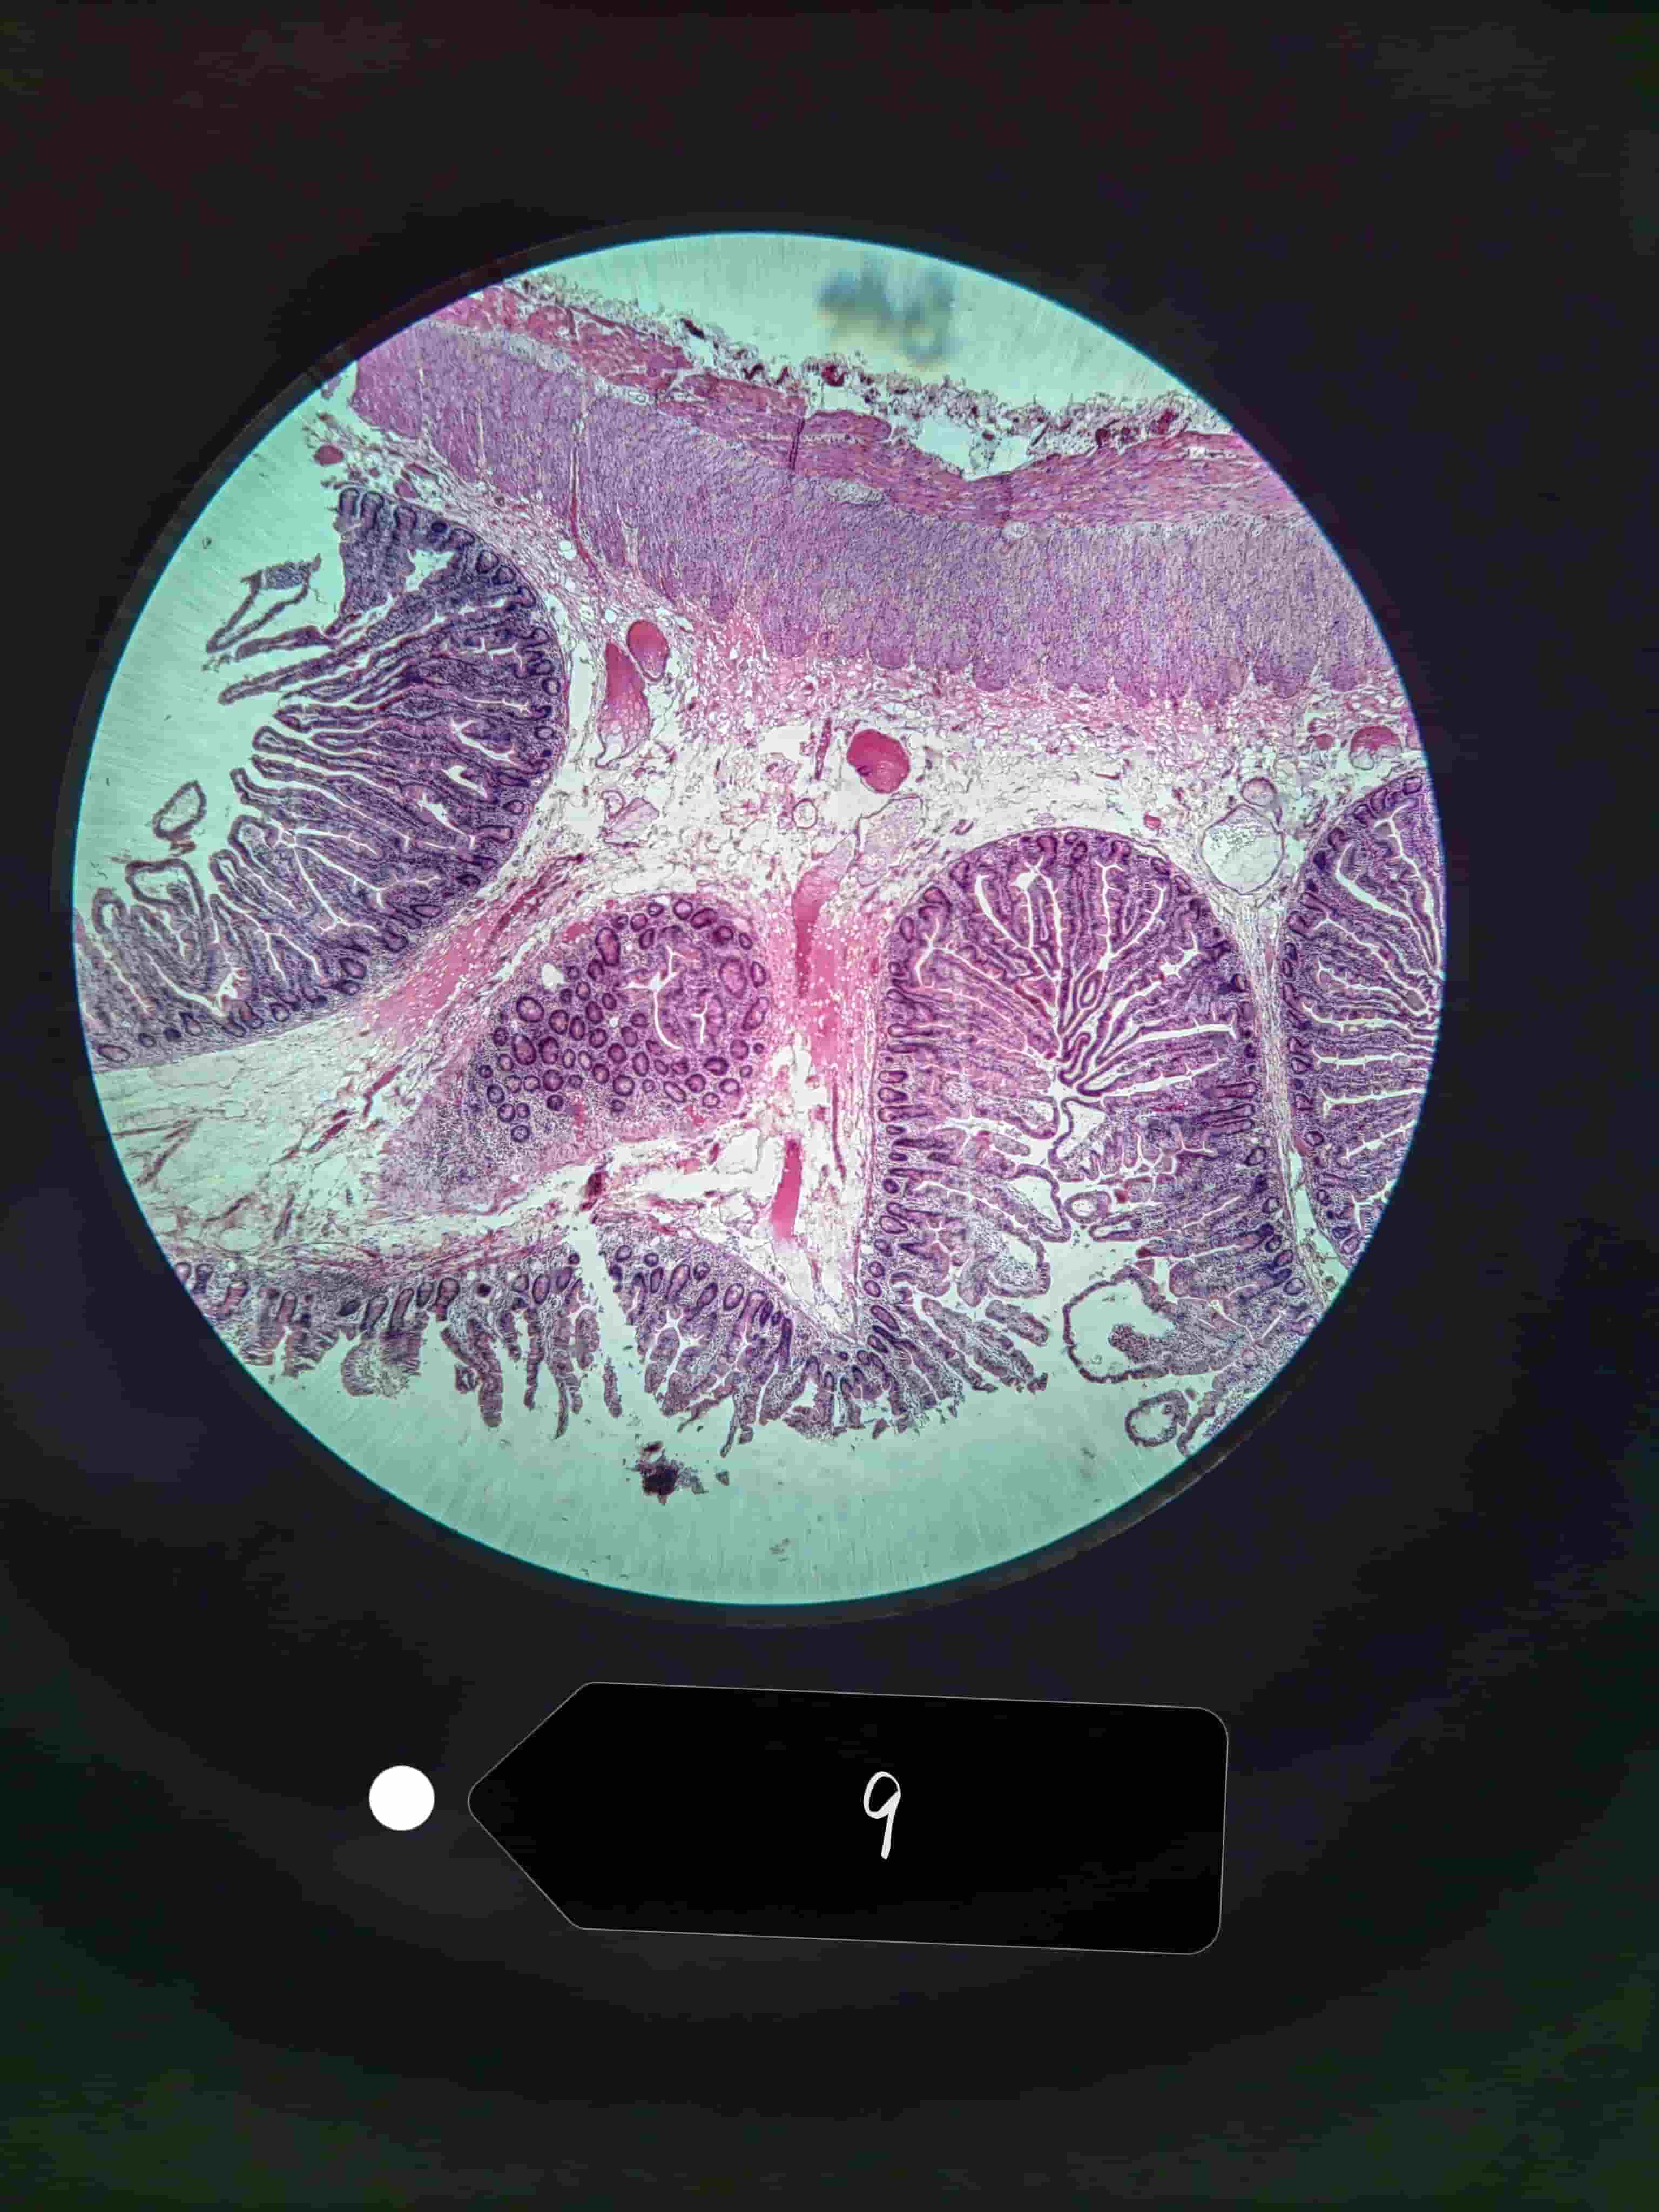

小肠

小肠绒毛

小肠腺,潘氏细胞